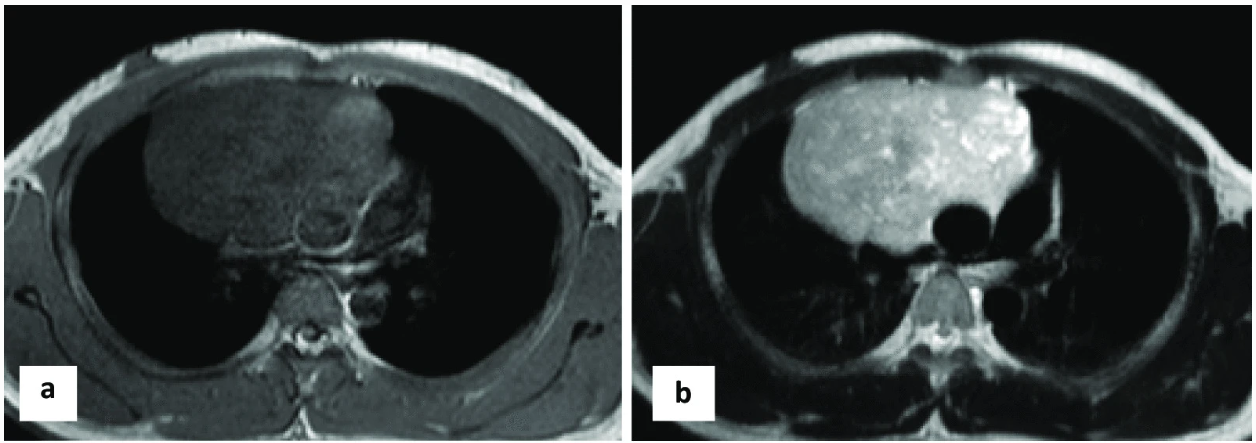

Mediastinal tumors grow at different rates depending on the type of tumor. For example, lymphomas typically grow fast, requiring urgent medical attention for the best possible outcome, whereas thymomas tend to grow more slowly, but still need careful monitoring5. Imaging techniques, such as CT and MRI scans, are essential in detecting abnormalities and monitoring how well the tumor responds to treatment.

Imaging techniques like CT and MRI scans are great tools for detecting abnormalities, such as mediastinal masses and tumors1. They can help determine the tumor’s size, shape, and whether it has spread.